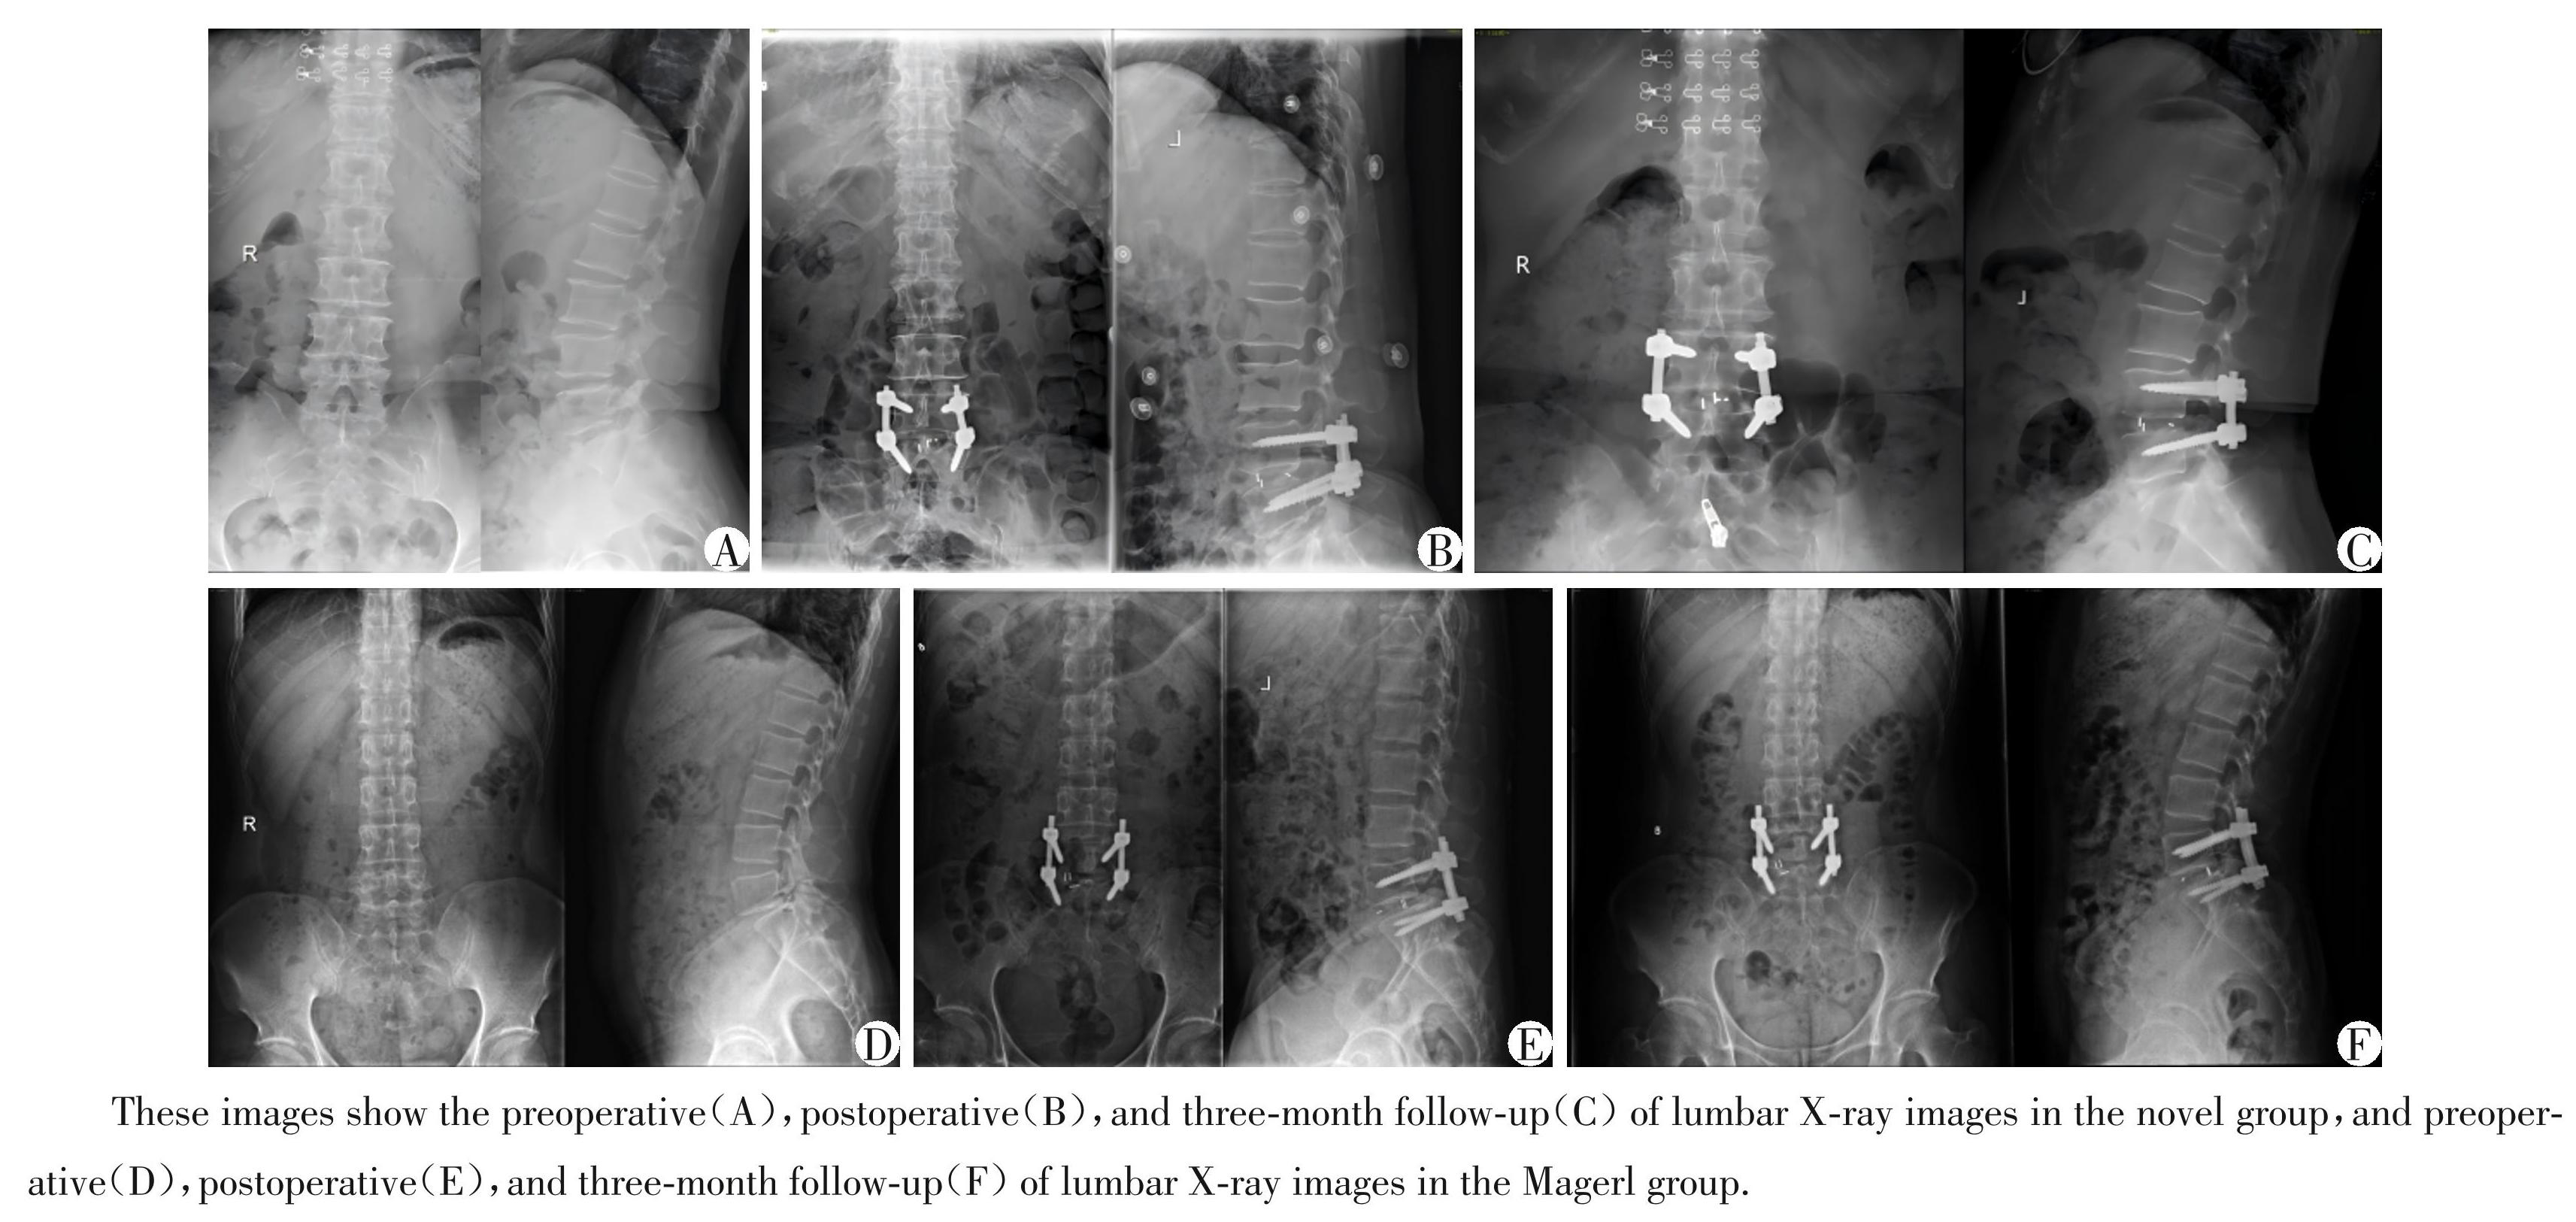

在所有腰5椎弓根螺钉的置入过程中,术中均未进行螺钉位置的调整。在Novel组中,A级和B级螺钉数量共57枚,C级和D级数量共3枚,皮质穿破率为 5%,置钉满意度为 95%;而 Magerl 组共 48 枚 A 级和B级螺钉,12枚C级和D级螺钉,皮质穿破率为20%,置钉满意度为80%(表3)。Magerl组的置钉满意度显著低于 Novel 组,差异有统计学意义(χ2 = 6.171,P=0.013,表3)。两组患者典型病例的X线检查结果见图2。

图2两组典型病例腰椎的影像学资料

Figure2Lumbar spine X⁃ray images of representative cases in the two groups